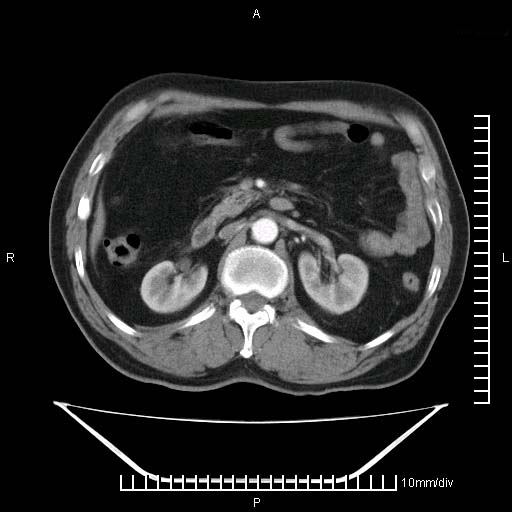

标题: CT25082:肝脏增强:男性,70岁 [打印本页]

标题: CT25082:肝脏增强:男性,70岁

患者以心脏疾病收住院,腹部无明显症状,b超查肝脏有占位。

牛眼征,中心坏死无强化,外缘强化,最外缘又见低密度,考虑转移,与脓肿鉴别

肝内多发转移瘤,右下肺炎症并少量胸水。胃壁增厚建议胃镜,胰尾部“病变”为肠管。

1)肝脏多发性转移瘤(不排除胰尾癌转移所致可能)。2)腹水。3)右侧少量胸腔积液。

ct25082 结果:转移瘤

外院mr结果:胰尾恶性占位。